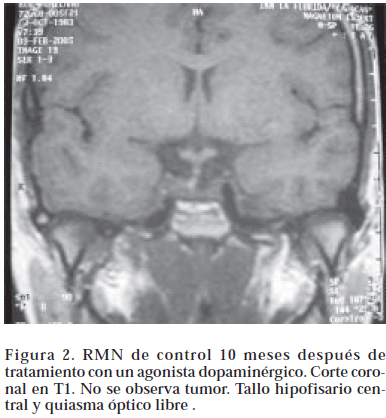

Los prolactinomas se clasifican de acuerdo a su tamaño en micro o macroadenomas Los primeros tienen menos de 10 mm de diámetro y se asocian con valores mas bajos de prolactina sérica. Los macroprolactinomas tiene más de 10 mm. y pueden a su vez comportarse en forma agresiva invadiendo los senos cavernosos, el seno esfenoidal y la cisterna supraselar5. Debido a que la cirugía transesfenoidal, normaliza los valores de prolactina solo en un 50 a 70% de los microadenomas6, esta es inefectiva en la mayoría de los macroadenomas y la recurrencia de la enfermedad es muy frecuente en el postoperatorio. El tratamiento con bromocriptina es la primera opción terapéutica en los prolactinomas. En dosis de 2,5 hasta 10 mgs por día, este medicamento normaliza los niveles de prolactina en 80 a 90% de los casos, disminuye el tamaño del tumor y mejora los campos visuales7(Fig 1 y 2). Los efectos secundarios se relacionan generalmente con la forma de administración de la droga, que debe tomarse fraccionada dos o tres veces al día y siempre con las comidas.